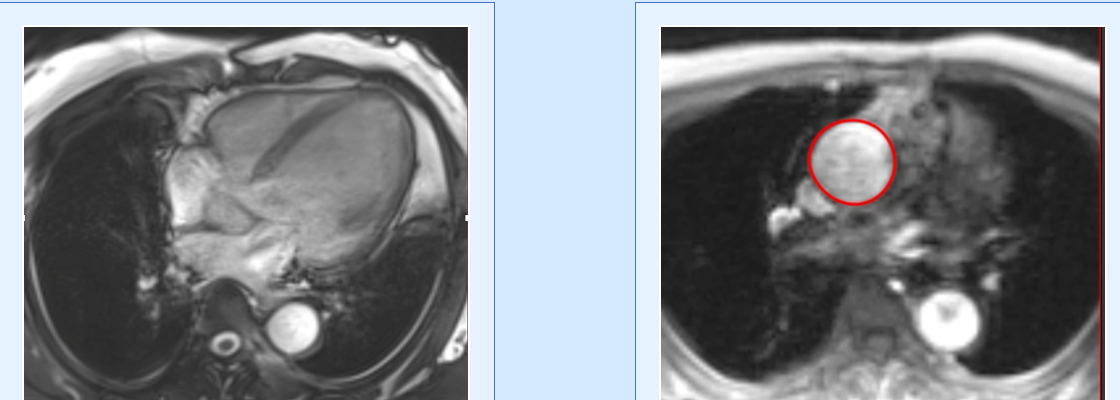

Cardiac MRI is a useful tool to diagnose amyloidosis. T1 mapping has become a mainstay, both native and ECV measurements. ECV measurement can now help quantify the amyloidosis burden and may help guide treatment based on how the ECV responds to specific treatment measures.